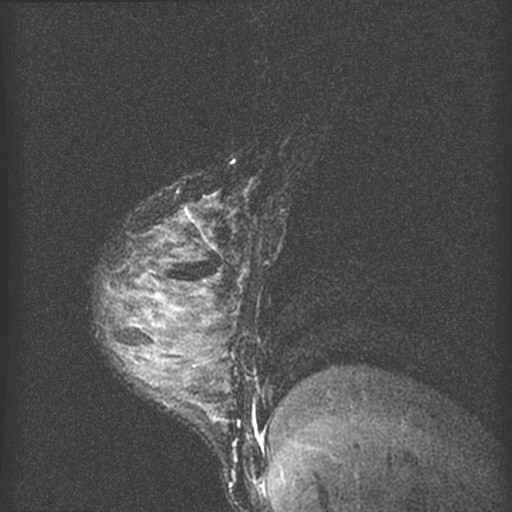

borst